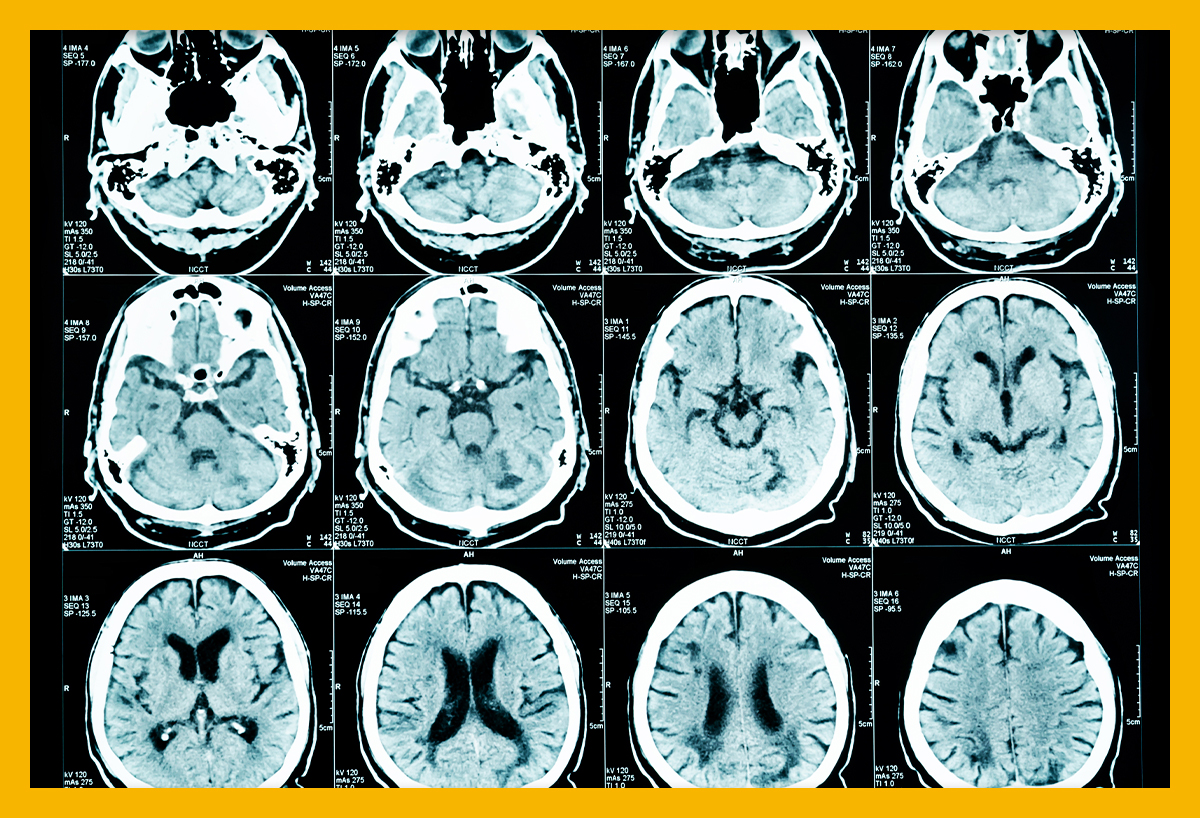

먼저, 뇌경색이 무엇인지에 대해 간단히 설명드리겠습니다. 뇌경색은 뇌에 공급되는 혈액이 차단되어 뇌세포가 손상되는 상태를 의미합니다. 대개 두 가지 종류가 있으며, 하나는 혈전으로 인한 허혈 뇌경색이고, 다른 하나는 출혈로 인한 뇌출혈입니다. 이 두 가지 모두 뇌에 큰 영향을 미치며, 생명을 위협할 수 있는 심각한 질환입니다.